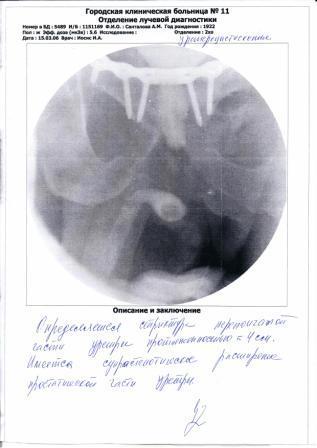

В сентябре 2014 г. меня сбила машина. Сломан таз с разрывом уретры.

В марте 2015 г. я был обследован в урологическом отделении Новосибирской больницы.

Необходима операция по восстановлению уретры.

Приложение: Выписки из истории болезни и уретроцистоскопия.